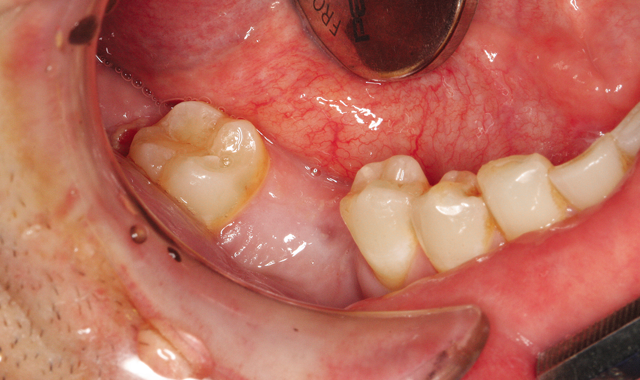

Fig. 2 Panoramic radiograph

I also take a panoramic radiograph (Fig. 2). These diagnostic tools not only aid in determining if a patient is a suitable candidate for implants, but also facilitate patient communication and case acceptance.